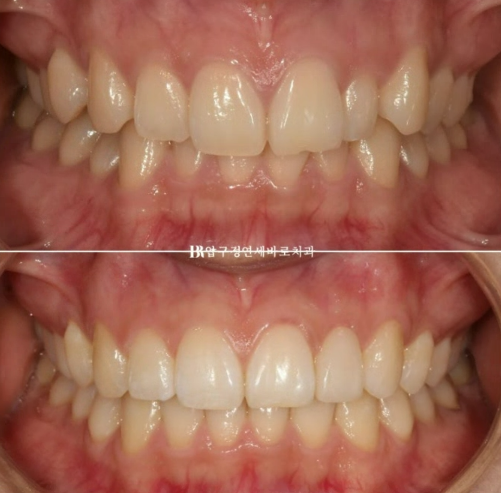

23.10~24.05

파란 화살표 왜소치는 정상크기로 치료가 되었습니다.

삐뚤한 앞니도 가지런해졌습니다.

앞니 교정으로 이 많은 것들이 좋아졌습니다.

미소는 자연스럽게 개선이 됩니다.